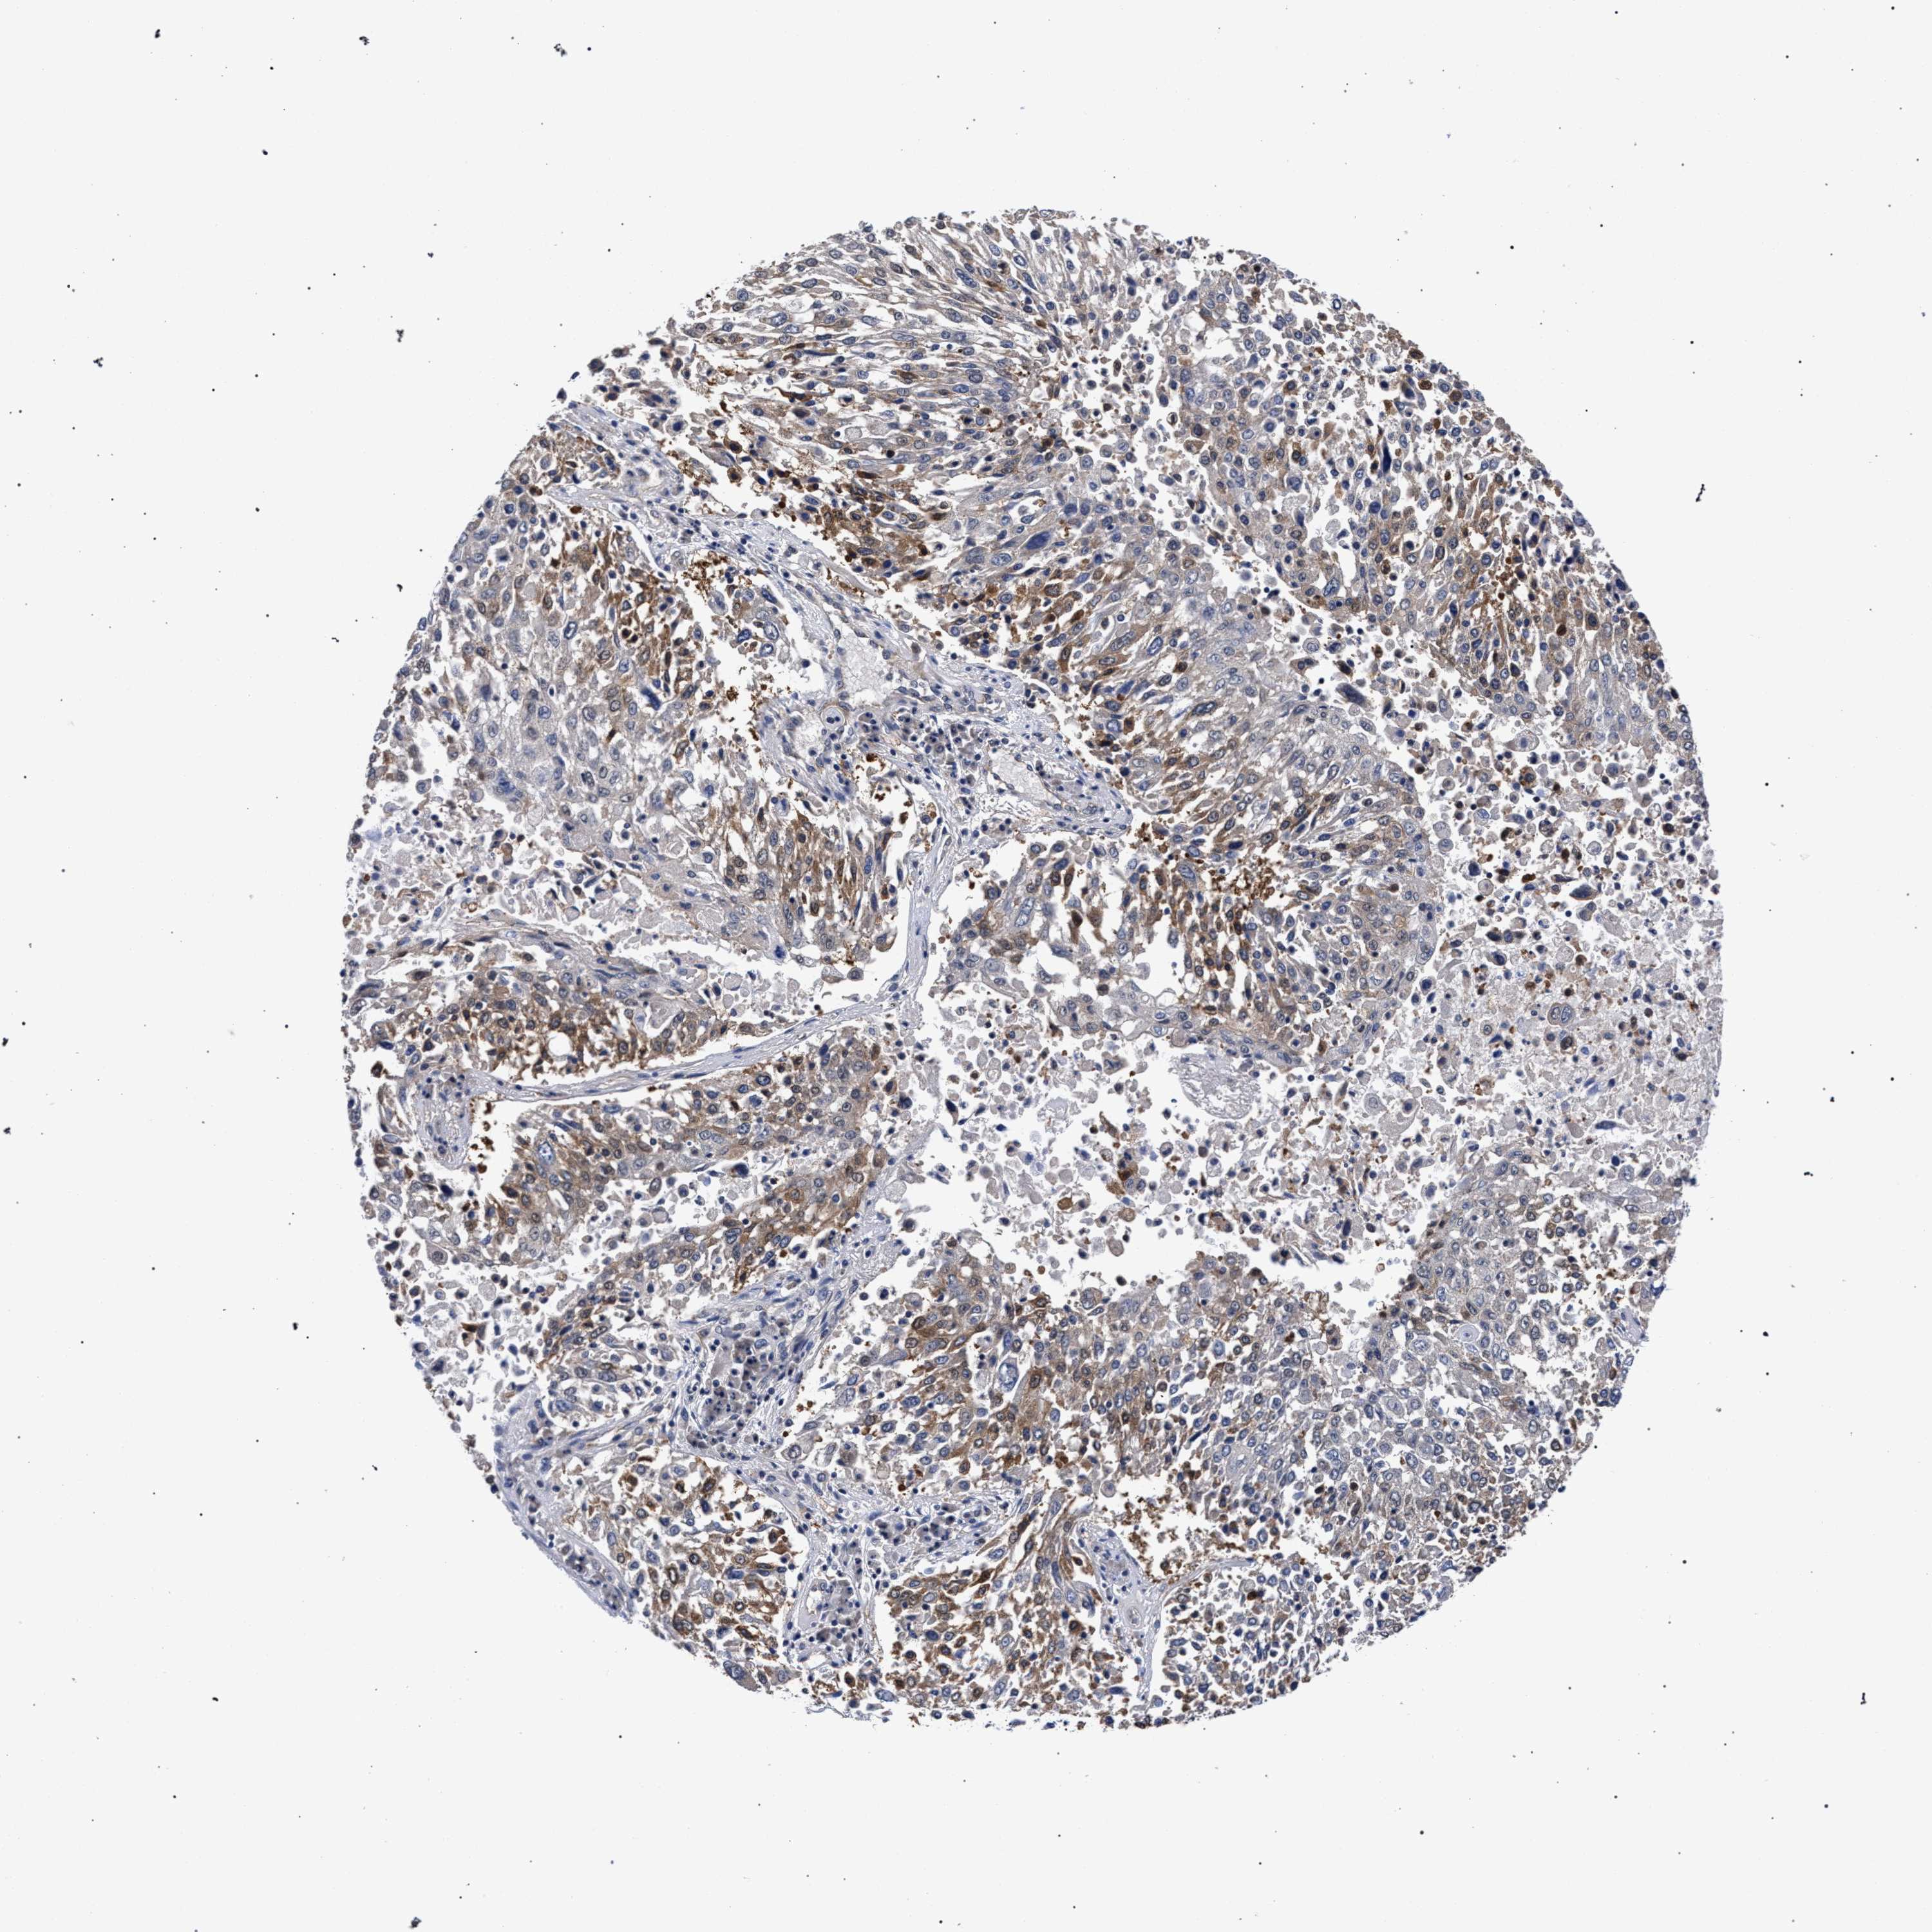

CANCER LUNG CANCER Show tissue menu

Lung cancer

Human cancer

Lung adenocarcinoma

Lung squamous cell carcinoma